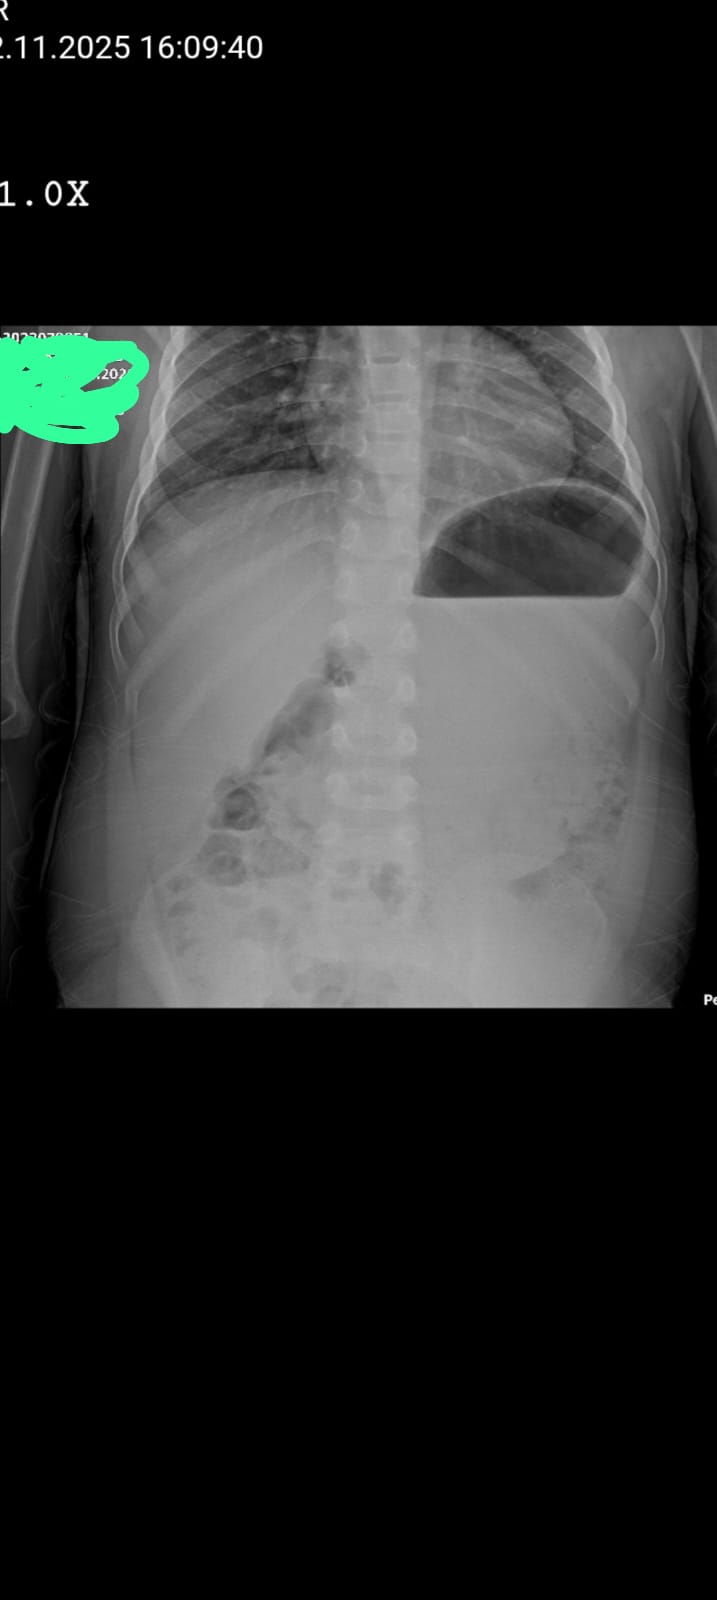

yarin sonuçlara gidecem ama görüntü siyahlık şey ne çok korkuyorum anlayan varsa bakabilirmi

Sol taraf kalp izasindaki karartı büyük yuvarlak görünsn

Elbette. Bu bir ayakta direkt karın grafisi (veya muhtemelen göğüs alt kısmı/üst karın bölgesini de içeren bir düz grafi) gibi görünüyor.

Röntgen, esas olarak göğüs kafesinin alt kısmını ve karın üst kısmını gösteriyor. Dikkat çeken en belirgin bulgular şunlardır:

* Sol Üst Kadranda Geniş Gaz Gölgesi ve Sıvı Seviyesi: Midenin olması gereken yerde, diyaframın hemen altında, büyük bir hava-sıvı seviyesi (air-fluid level) görülmektedir. Bu, midedeki (veya karındaki başka bir organdaki) sıvı ve gazın ayrılmış halidir ve ayakta çekilen grafilerde normal mide gazı kabarcığının daha belirgin/geniş bir hali olabilir.

* Normalde: Midenin üst kısmında (mide fundusunda) küçük bir gaz kabarcığı normaldir. Buradaki gaz kabarcığı ve sıvı seviyesi oldukça belirgin ve büyüktür.

* Akciğer Alanları:

* Sağ Akciğer: Sağ diyaframın hemen üzerinde akciğer dokusu görülmekte ve belirgin bir patoloji (büyük bir infiltrasyon, pnömotoraks, vs.) hemen göze çarpmamaktadır.

* Sol Akciğer: Sol diyaframın üzerinde de akciğer dokusu görülmekle birlikte, alt kısım büyük gaz gölgesi ile komşudur.

* Serbest Hava (Pnömoperitoneum) Arayışı: Karın boşluğunda, diyafram altında veya karın organları arasında serbest hava (pnömoperitoneum) olup olmadığı, özellikle karın içi organ perforasyonlarında (delinmelerde) önemlidir. Bu grafide, sağ diyafram altında bariz bir serbest hava (hilal şeklindeki bir hava gölgesi) hemen göze çarpmamaktadır, ancak bu tür bulguların tespiti bir uzmanın işidir.

* Bağırsak Gaz Dağılımı: Alt karın bölgesinde bağırsak gazlarının dağılımı görülmektedir. Bağırsak anslarının (kıvrımlarının) belirgin şekilde genişleyip genişlemediği (obstrüksiyon/tıkanıklık açısından), gazın ince veya kalın bağırsakta ağırlıklı olup olmadığı (barsak tıkanıklığı varlığında) dikkatli incelenmelidir.

Bu gözlemler, sadece bir görüntü üzerindeki radyolojik dansiteler (yoğunluklar) ve anatomik yapıların genel bir tarifidir. Bu görüntünün neden çekildiğini, hastanın klinik durumunu (şikayetleri, ateşi, ağrısı vb.) ve tıbbi geçmişini bilmeden bir anlam ifade etmez.

Lütfen bu görüntüyü acilen bir doktora veya radyoloji uzmanına gösterin.